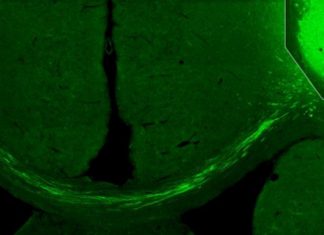

Common Weed Stops the Growth of Breast Cancer Cells, Scientists in London Report